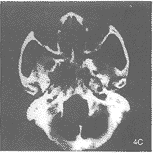

颅底海绵窦复发:出现新的颅底骨质破坏伴咽壁占位15例,占20.5%。还有7例伴海绵窦增大变形,并明显强化。同时伴破裂孔扩大及咽壁占位,占9.6%(图4)。

图4 A.鼻咽右侧壁及后壁占位,右侧卵圆孔较对侧略大。

B.放疗后示鼻咽各壁呈放疗后改变,颅底未见骨质破坏。

C.鼻咽右侧壁占位,及以右侧为主的蝶骨大翼、右侧岩尘广泛骨质破坏,右侧海绵窦受侵